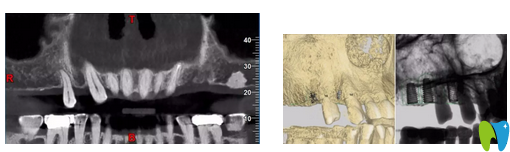

CT片顯示14區(qū)缺牙間隙較狹窄

CBCT顯示:14區(qū)缺牙間隙較狹窄,模擬植入后,近遠(yuǎn)中距臨牙安 全距離不足1.5mm;其余缺牙區(qū)骨質(zhì)及骨量的情況,以及距離上頜竇底高度均基本滿足種植要求。缺牙區(qū)咬合高度基本滿足后期修復(fù)要求。